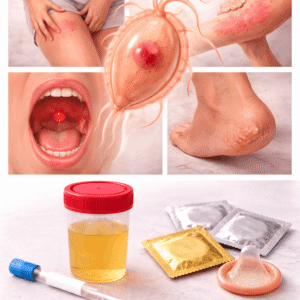

STD-testit ja hoidot

Ymmärrä STD-testit ja hoidot Sukupuolitaudit (STD), joita kutsutaan myös sukupuolitautitartunnoiksi…

Sukupuolitaudit

Mitkä ovat sukupuolielinten infektiot ja miksi niitä esiintyy? Sukupuolielinten infektiot…

Opas sukupuolitauteihin (STD) liittyvään testaukseen ja hoitovaihtoehtoihin

Sukupuoliteitse tarttuvat taudit (STD) voivat vaikuttaa kehen tahansa, mutta niiden varhainen havaitseminen…